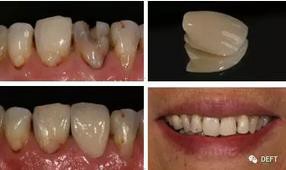

15.氧化鋯修復(fù)體的美學(xué)外觀有改良么?

在過去的三年,氧化鋯修復(fù)體的美觀程度大大提高。這項(xiàng)趨勢還將延續(xù),在以愛爾創(chuàng)“玉瓷”(透度高達(dá)49%)為代表的新型氧化鋯產(chǎn)品的不斷推出,相信最終會(huì)達(dá)到及超越烤瓷冠的外觀。(圖8)

360截圖20170125143722921.jpg

圖8  愛爾創(chuàng)-UPcera“玉瓷”全鋯冠前牙修復(fù)